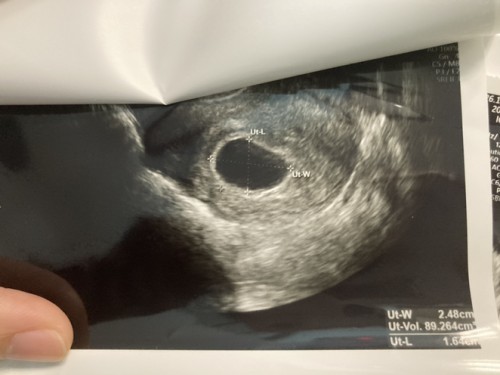

อายุครรภ์ 8 วีค ค่า hcg จากการตรวจเลือด 34,933 เเต่ยังไม่เห็นน้องเลย มีโอกาสท้องลม มั้ยคะ ?